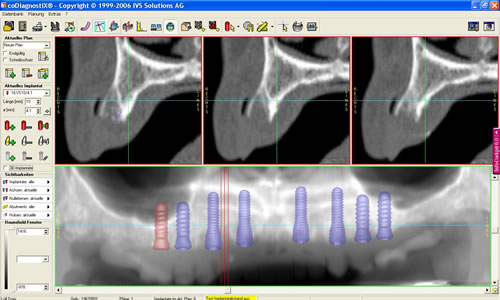

Mit der Entwicklung der Computertomographie (CT) und in jüngerer Vergangenheit der digitalen Volumentomographie (DVT) stehen Untersuchungsverfahren zur Verfügung, mit denen sehr viel einfacher und genauer das Knochenangebot vermessen werden kann. Von dem Patienten wird in einer Klinik oder Praxis, die über die entsprechenden Möglichkeiten verfügt, ein Spezialröntgenbild (DVT/CT) des Ober-, seltener des Unterkiefers, angefertigt. Dieses spezielle Röntgenbild dauert für einen Kiefer 20 Sekunden. Der große Vorteil liegt darin, dass der gesamte Kiefer durch den Computer in über 100 Schnitten abgebildet werden kann. Auf diesen Schnittbildern können Höhe und Breite des Knochens direkt abgemessen werden (Abb. 5.5).

Am Praxiscomputer lassen sich Besonderheiten des jeweiligen Patienten herausarbeiten, wie z. B. die Beschaffenheit der Nasennebenhöhle. Hier können verschiedenen Knochenleisten (Abb. 5.6) oder Schleimhautveränderungen das Implantieren erschweren. Umso wichtiger ist es durch ein Computertomogramm diese Variationen vor der Implantation zu kennen. In den speziellen Programmen können bereits Implantationen simuliert werden (Abb. 5.7, 5.8).

Abb. 5.7: Implantations- simulation am PC.

Abb. 5.8: Implantatplanung.

Dabei werden das Implantat, die richtige Länge und der geeignete Durchmesser ausgewählt. Entscheidend ist auch die Richtung, in der implantiert werden muss. Auch dies lässt sich bereits am Computer auf den Schnittbildern simulieren. Eine dreidimensionale Darstellung des Knochens und die Möglichkeit das äußere Profil zu zeigen, verdeutlichen den späteren Sitz der Implantate und die Beziehung zum Gegenkiefer, zur Kauebene, zu Wangen und Lippen lassen die spätere Versorgung kosmetisch vorhersehen (Abb. 5.9, 5.10). Eine Dichtemessung um die Implantate schließt die Planung ab.

Im Oberkiefer wird diese Untersuchung und Planung in unserer eigenen Praxis seit Jahren routinemäßig durchgeführt. Die erheblich verbesserten Ergebnisse rechtfertigen den Mehraufwand, die geringfügig höhere Strahlenbelastung der heutzutage modernen Geräte sowie die Kosten, die dadurch entstehen.

Für den Oberkiefer ist eine CT-Untersuchung notwendig, die ebenfalls mit einer Schablone durchgeführt wird. Auswertung, Planung und Implantations-Simulationen ergeben, dass sechs Implantate im vorderen Kieferabschnitt verankert werden können. Auch die Qualität des Knochens lässt eine Einpflanzung ohne weitere Maßnahmen zu. Diese Behandlung soll nach der Versorgung des Unterkiefers erfolgen.